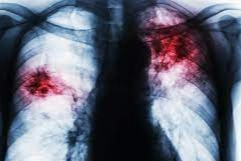

Akciğer embolisi, kalbin sağ tarafından çıkan ve akciğere giden pulmoner arterlerin kan pıhtısı, hava ya da yağ gibi maddelerle tıkanması sonucu ortaya çıkan ciddi ve hayati risk taşıyan bir sağlık durumudur. Genellikle damarlarda kan pıhtılaşması sonucu oluşurken, daha nadir olarak hava veya yağ embolisi şeklinde de görülebilir. Akciğer embolisinin temel nedenleri arasında damarların iç yüzeyinde meydana gelen hasar, kan akışındaki yavaşlama (staz) ve pıhtılaşma eğiliminin artması (hiperkoagülabilite) yer alır.

Bu sağlık problemi, vücudun alt bölümlerinde, özellikle bacak ve karın bölgesindeki toplardamarlarda oluşan pıhtıların, kalbin sağ ventrikülüne ve oradan pulmoner arterlere taşınmasıyla meydana gelir. Akciğerlere ulaşan pıhtı, damarları tıkayarak o bölgedeki kan dolaşımını ve oksijen alımını bozar. Bu durumun şiddeti, tıkanan damarın büyüklüğüne bağlı olarak değişir ve büyük damarların tıkanması durumunda sonuçlar daha ağır olabilir.

Belirtiler arasında ani nefes darlığı, göğüs ağrısı, öksürük, bazen kanlı balgam, şiddetli göğüs baskısı ve bayılma yer alır. Akciğer embolisinin tanısı, hastanın hikayesinin iyi bir şekilde alınması ve emboli ihtimalinin göz önünde bulundurulmasıyla başlar. Kesin tanı için genellikle kontrast madde verilerek çekilen akciğer tomografisi ve bacaklara yapılan doppler ultrason kullanılır.